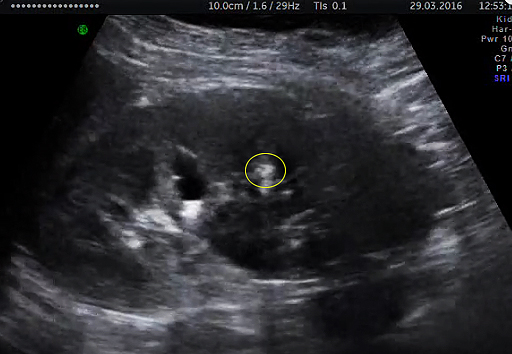

Конкремент?

Ваши мнения,коллеги.

В той области которую показываете я лично конкремент не увидел. гиперэхогенность могу связать с эффектом дорзального псевдозвукоусиления от расширенной чашечки. .

на последних секундах ролика отчетливо видно гиперэхогенное гладкое овальное образование в расширенной верхней чашке без акустической тени ,виден в разных положениях и при ЦДК , расценила как конкремент.

Странно почему вы видите овальное образование при поперечном сканировании и напрочь игнорируете то, что оно вытягивается в стенку чашечки при продольном сканировании (примерно середина ролика). И на основании чего не имея акустической тени можно утверждать, что это конкремент?

Простите но про акустическую тень это не ответ. Не подтверждая свои слова четкими ультразвуковыми признаками мы можем такого нагородить, что потом не расхлебаем.видела во всем ролике конкремент, в конце он лучше выделился на фоне чашки,а акустическая тень видна не при всех камнях (все мы об этом знаем )

Нет это не кальциевое молочко. это простая стенка чашечки которая видна более эхогенной за счет того, что ультразвуковые волны лучше проходят через жидкость в чашечке и "подсвечивают" ткани находящиеся позади.

А в отношении мелкого камня я сто раз бы подумал, прежде чем указывать его в заключении 9-ти летней девочке, при сомнительных УЗ-признаках